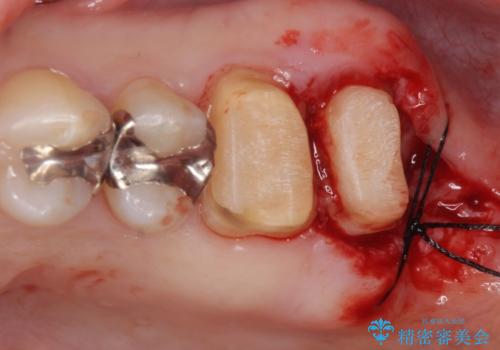

- 銀歯をやりかえたいが他院で抜歯と言われセカンドオピニオンで来院。適合の悪い被せ物が入っており、まずは古い材料、虫歯をとり保存可能か確かめる必要があり、拡大鏡下で全て取り除いたら歯質が歯茎の中まで虫歯がありました。このまま無理やり型取りをして被せ物を作っても不適合な被せ物が入る可能性が高いため歯茎を切り取る手術(ディスタルウェッジ)を行いました。そして再根管治療を行いゴールドの被せ物で治療を行いました。

- PGAクラウン・仮歯 13.2万円×2 精密根管治療(リトリートメント)・コア 16.5万円×2 ディスタルウェッジ 1万円費用は治療当時の料金となります